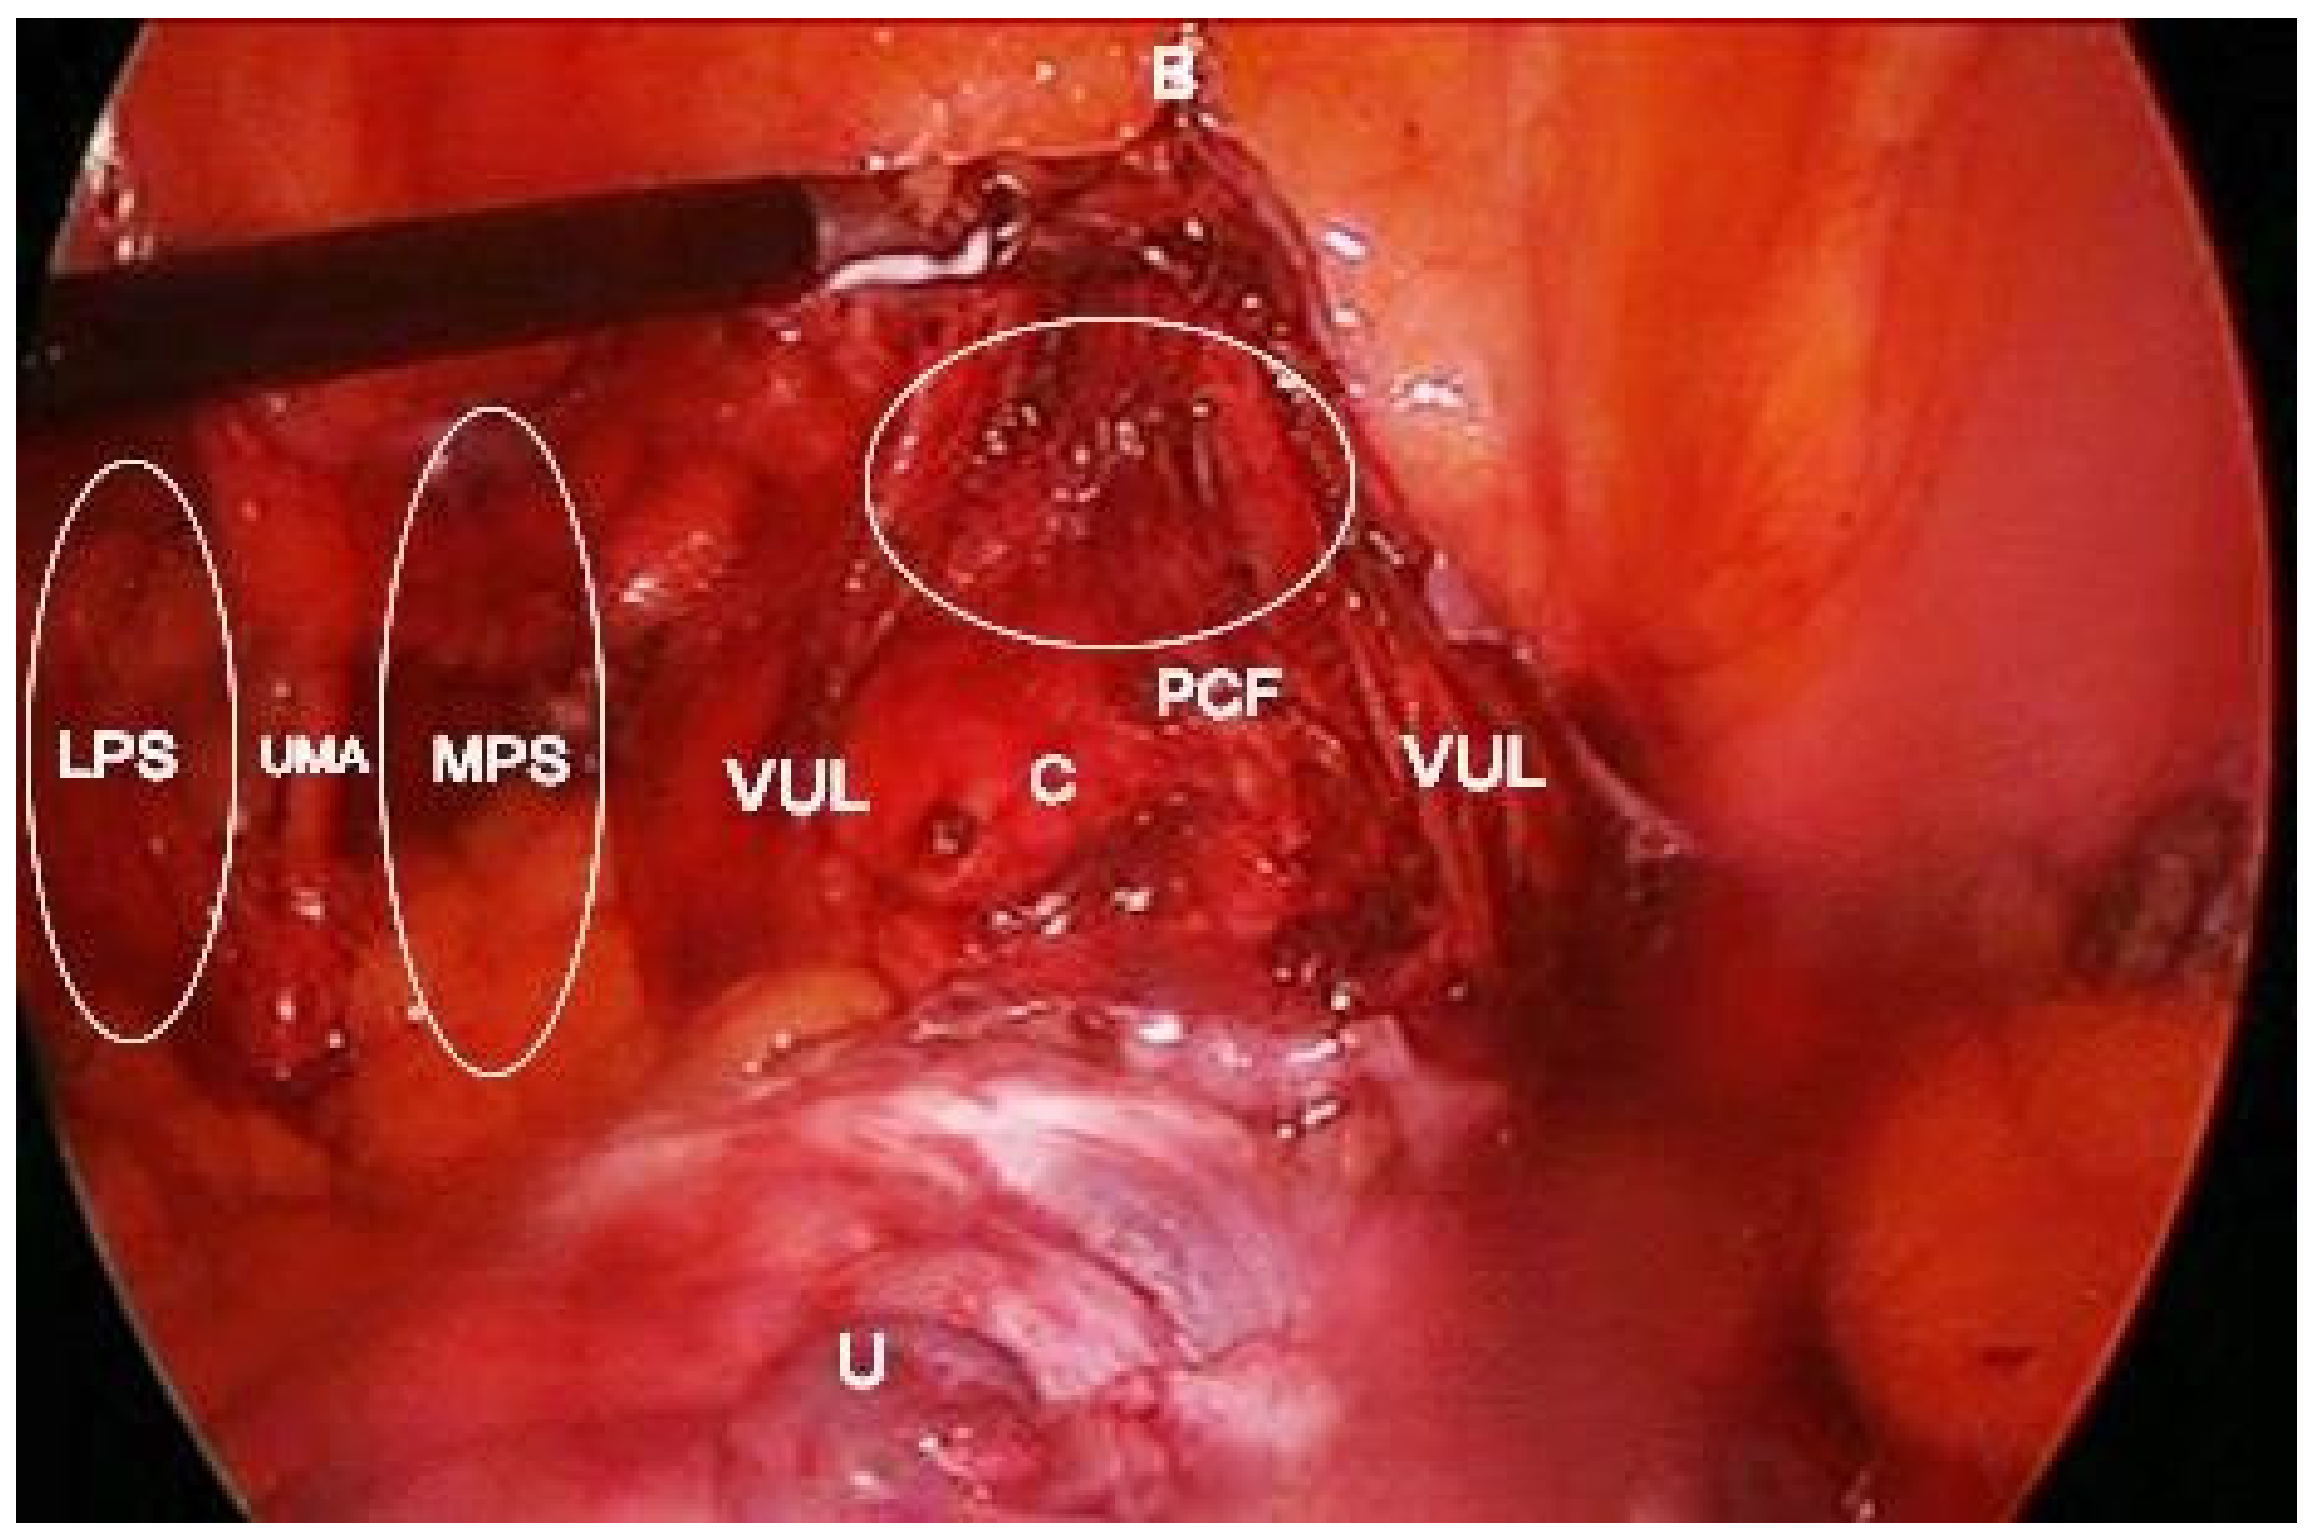

Paravesical space boundaries: ventrally-superior pubic ramus, arcuate line of the os ilium; dorsally–cardinal ligament including parametrium (over the ureter) and paracervix (below the ureter), uterine artery/vein; medially-caudal portion of vesico-uterine ligament, bladder; laterally–obturator internus fascia/muscle, external iliac artery/vein. The paravesical space is covered by the peritoneum of the anterior leaf of broad ligament. Its floor is the ilio-coccygeus muscle and pubocervical fascia as it inserts into the arcus tendinous fascia pelvis [1,4,5,8,9,10,11]. Some authors consider the paravesical space as a lateral compartment of the Retzius space [8]. Paravesical space contains the umbilical artery, superior vesical artery, the obturator neurovascular bundle, lymphatic tissue, and accessory obturator vessels [10]. The obliterated umbilical artery and umbilical pre-vesical fascia divides this space into lateral paravesical space (LPS), and medial paravesical space (MPS), respectively [7,9] (Figure 2, Figure 3 and Figure 4).

The space within the LPS is known as obturator space. This space has the same boundaries as the paravesical space, except for a medially–superior vesical artery. The obturator space contains an obturator nerve/artery/vein, loose areolar, and lymphatic tissue [8]. The paravesical space is dissected by transecting the round ligament and cutting the anterior leaf of broad ligament ventrally and laterally to the obliterated umbilical artery [5]. Transecting the round ligament is not a necessary step. In our opinion, it is not necessary to transect the round ligament when performing laparoscopic pelvic lymphadenectomy previous to radical hysterectomy. The obliterated umbilical artery is identified and after ventral dissection, the paravesical space is opened to the level of levator ani muscle for the MPS and obturator nerve for LPS, respectively [5,7,9]. LPS and MPS can be dissected through laparotomy or laparoscopic/robotic surgery, for various gynecological conditions. From an oncogynecological point of view, the paravesical space is laterally open, medializing all anatomic structures, whereas in a benign gynaecological condition, the paravesical space is opened from a medial aspect and goes lateral to enter the space [11].

Figure 12. Development of vesicovaginal space during laparoscopic total hysterectomy shown in empty ellipse. The bladder is pulled up with a grasper. B—bladder; U—uterus; MPS—medial paravesical space; LPS—lateral paravesical space; C—cervix; UMA—umbilical artery; VUL—cranial portion of the vesico-uterine ligament; PCF—pubocervical fascia.